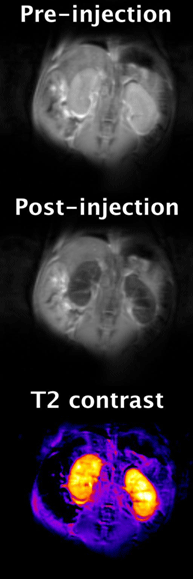

Magnetic resonance images of mouse kidneys at 9.4 Tesla showing the effects observed after injecting a 0.1 mmol/kg dose of a EuDOTA-based polymeric contrast agent. Uptake of the agent in the kidneys causes a 60% reduction in signal, making them appear dark (negative contrast). The negative contrast is caused by water molecule exchange between the Eu3+ ion and bulk water, which facilitates T2 exchange (T2exch). T2exch contrast is one on many novel methods used to further extend the functional and molecular imaging capabilities of MRI.

In vivo imaging of CEST (chemical exchange saturation transfer) and PARACEST (paramagnetic CEST) magnetic resonance contrast agents: CEST agents create contrast in MR

(magnetic resonance) images by exchanging their saturated Lanthanide bound protons with those of bulk water. Saturation is achieved by applying a 5 to 10 second long

frequency-specific pulse just before imaging. These agents have great potential to further extend the functional and molecular imaging capabilities of MR. Some

applications include measuring pH, angiogenesis, and glucose metabolism. We are currently investigating both monomer and polymeric Eu DOTA-(gly)4 based structures,

as well as a Eu DOTAM-based glucose sensor. We are also investigating several PARACEST imaging protocols including direct saturation and inversion-recovery (PCEST)

methods to help improve overall in vivo sensitivity.